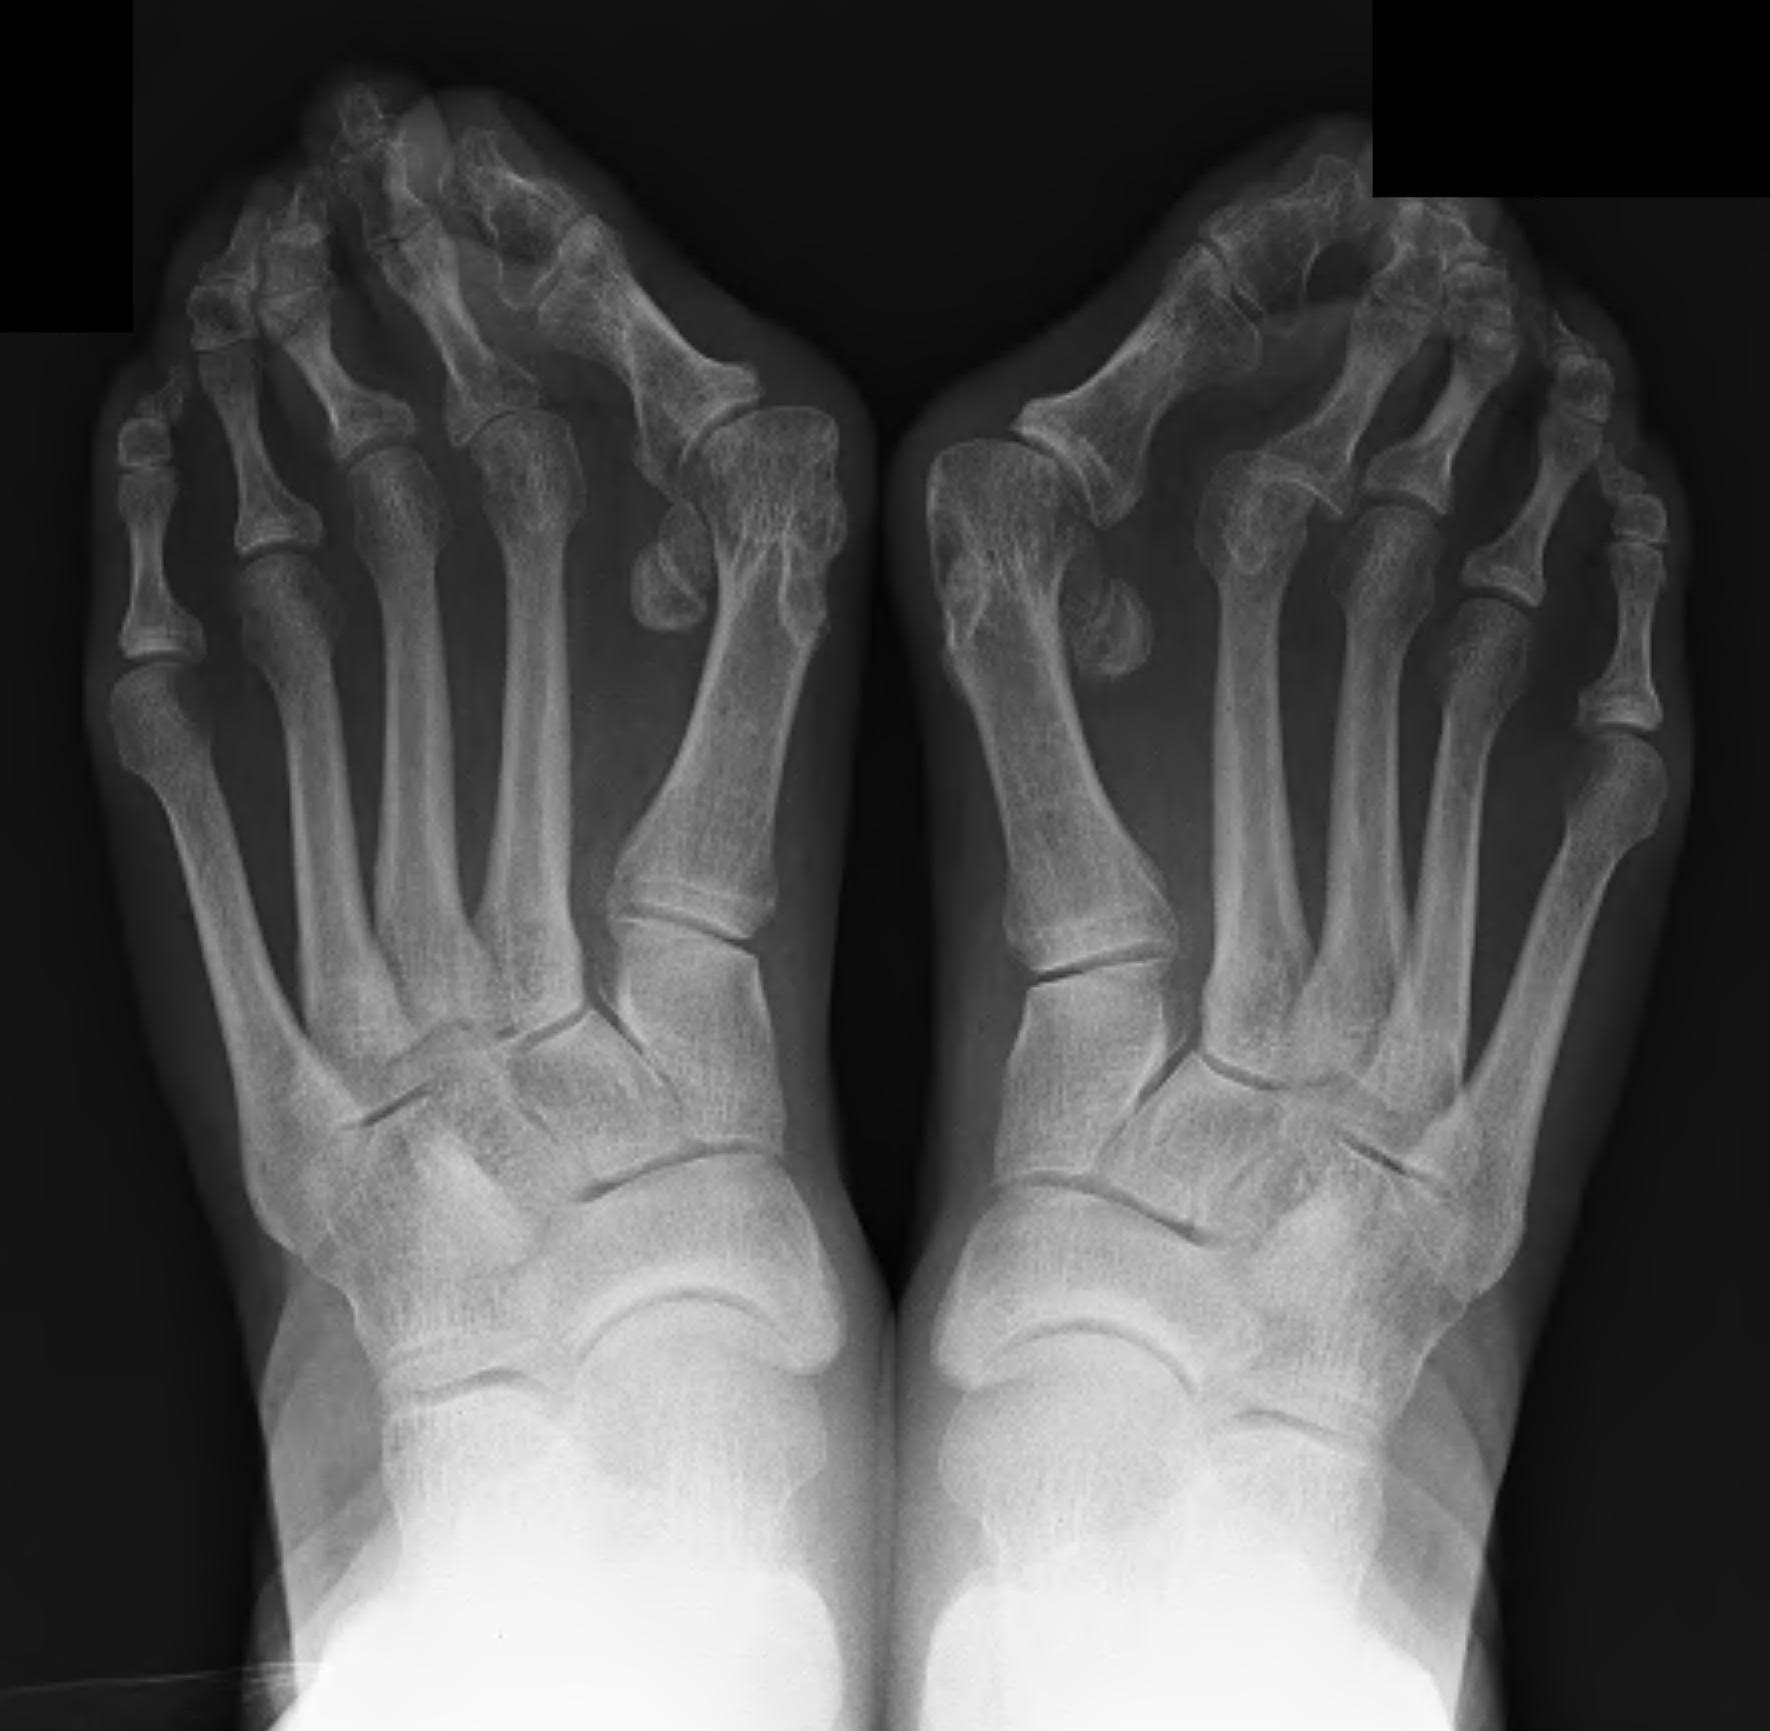

Weight Bearing AP X-ray

Angles

| HVA | DMAA | IMA | HVI |

|---|---|---|---|

|

HVA - hallux valgus angle - metatarsophalangeal angle (MTPA)

Normal < 15o |

Distal metatarsal articular angle

Intermetatarsal angle

Normal < 9o |

Hallux valgus interphalangeus

Normal <10o |

Other

| Joint congruence | Sesamoid subluxation | TMT joint obliquity |

|---|---|---|

Dots on articular surfaces - metatarsal head - base P1 |

Amount of lateral sesamoid uncovered |